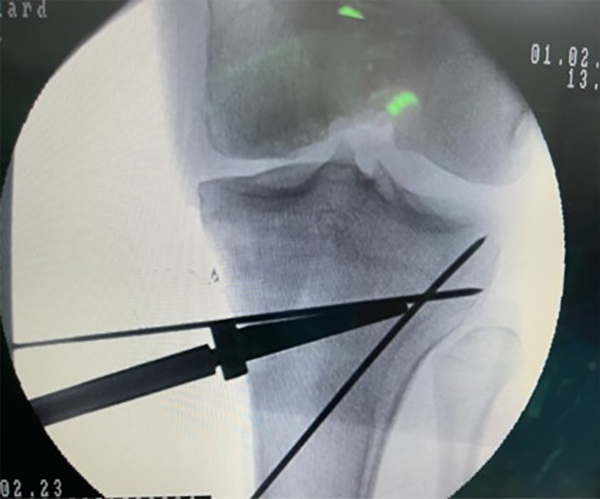

Sin embargo, esto es un dato que debe ser corroborado intraoperatorio ya que la longitud de la osteotomía puede variar. Teniendo el ángulo de corrección, e intraoperatorio, y la longitud exacta de la misma, sólo debemos obtener el dato de esta fórmula trigonométrica y los milímetros de apertura; esta sería la tercera forma de corroborarlos de manera intraoperatoria. La forma de aplicar este cálculo de los milímetros es obtener exactamente la apertura, o resección dependiendo el caso: en las figuras 20, 21 y 22 se puede observar la apertura y posterior medición para la corrección planeada.

Figura 20: Se observa intraoperatorio la forma de abrir la osteotomía con una cuña de 8 mm bajo intensificador de imagen.

Figura 21: Se evidencia la cuña manteniendo la apertura, pin de la osteotomía y su forma biplanar.

Figura 22: Obsérvese la apertura calculada en el planeamiento de 8 mm.